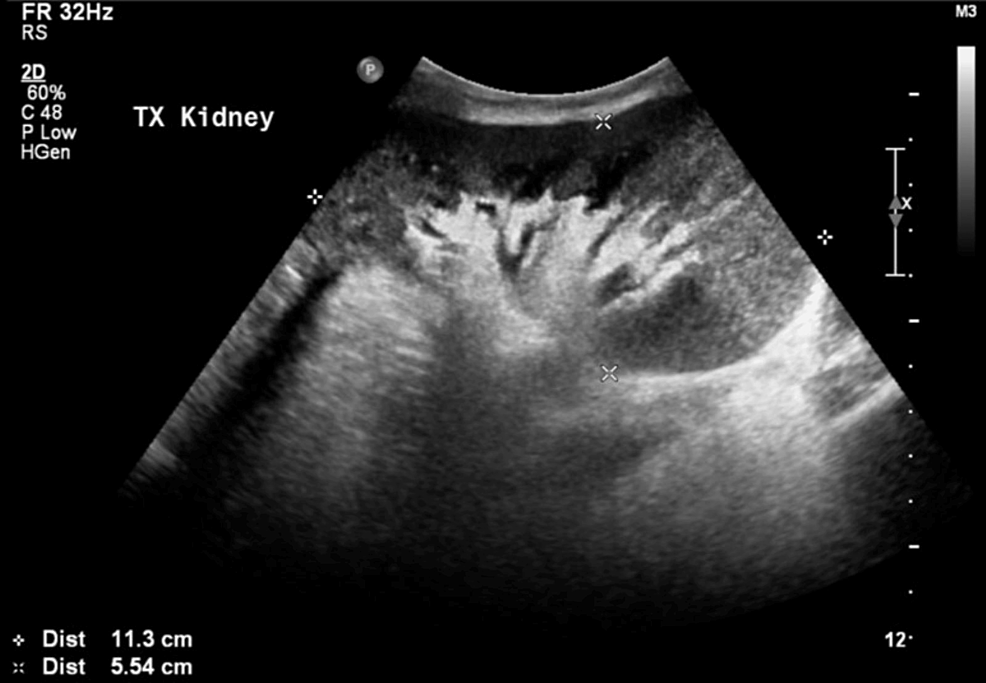

From kriznanultrasoundimages.com

CHRONIC KIDNEY DISEASE POST RENAL TRANSPLANT STATUS STABLE Post Kidney Transplant Seroma If drain fluid creatinine and potassium values are not dissimilar from the serum values, then the possibilities of. The common etiologies of perirenal fluid collections occurring after kidney transplantation include urinomas, hematomas,. In the immediate postoperative period, sonography is useful in diagnosing such surgical causes of delayed graft function as thrombosis of the renal artery or vein, urinary obstruction. In. Post Kidney Transplant Seroma.